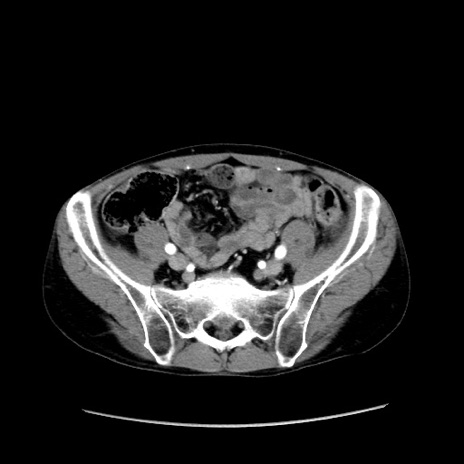

冠状断像

【症例】40歳代 男性

【主訴】腹痛

【現病歴】4時間ほど前に電車に乗車中に臍部上より腹痛出現。徐々に増悪し起立困難となり、救急外来受診。生ものは数日食べていない。今朝お雑煮を食べた。

【身体所見】BT 36.8℃、BP 117/84mmHg、HR 91/min、SpO2 97%、苦悶様、腹部:臍上部広範囲圧痛あり、反跳痛±

【データ】WBC 8100、CRP 0.03